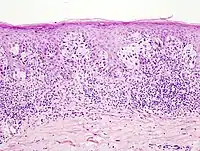

- Окончательный диагноз меланомы может быть установлен только после гистологического исследования, проведённого после тотального удаления невуса (опухоли) с достаточным захватом здоровых тканей. Предоперационная биопсия с помощью иглы или частичного удаления противопоказана, во избежание распространения меланомы. Определяется глубина прорастания (Clark, Breslow) и митотический индекс.

Микростадии по Clark 1967 г.

- Уровень I: все опухолевые клетки находятся в эпидермисе, до базальной мембраны

- Уровень II: клетки опухоли инфильтрируют сосочковый слой дермы

- Уровень III: опухоль достигает границы между сосочковым и сетчатым слоями дермы

- Уровень IV: опухолевые клетки обнаруживаются в сетчатом слое дермы

- Уровень V: опухоль прорастает в жировую клетчатку